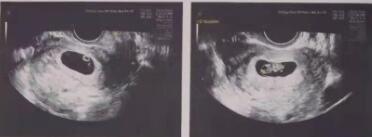

9月17日,李女士怀着忐忑的心情到中泌抽血验孕,拿到化验单的那一刻:HCG:637.7mIU/ml。数值清晰地告诉李女士:怀了!

李女士说自己移植之后感觉良好,后期回院做超声复查也无发现异常。与此同时,王燕医生细心交待李女士“毕业后”,孕期仍需到专业产科医院定期做好产检。